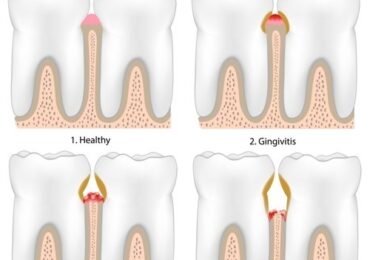

Routine Check-ups

Comprehensive dental check-ups for both children and adults.